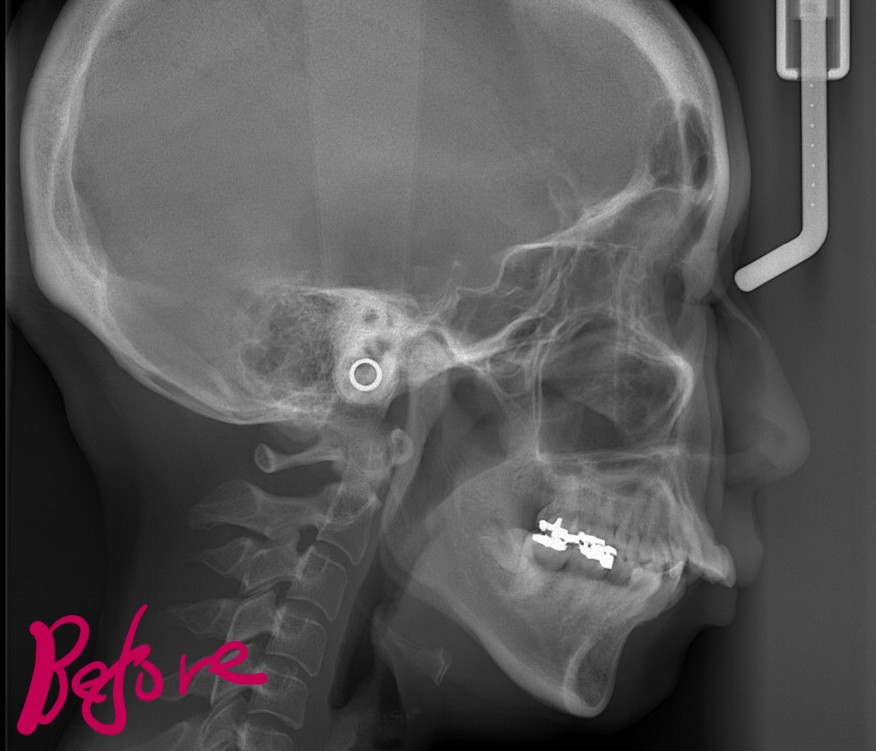

【Before】

レントゲン写真で確認すると、

この患者さんの場合、

では、矯正治療前後の「レントゲン写真」や「歯並び」「横顔と口元の写真」などを比較してみましょう。

まずはレントゲン写真の比較です。

左側が矯正治療前、右側が矯正治療後